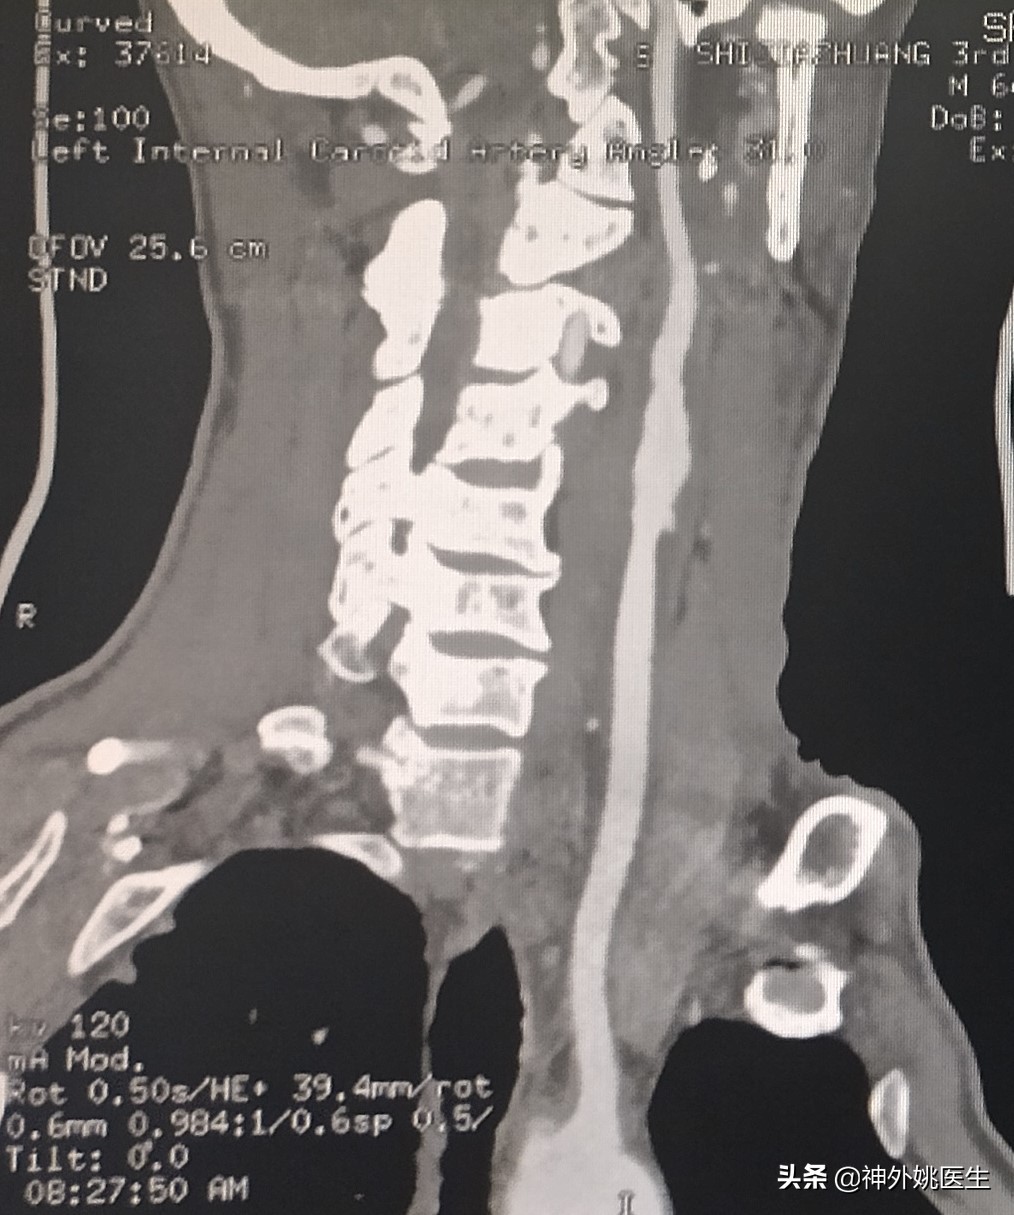

患者廉XX,男性,64岁。主因头痛、头晕,伴右侧肢体无力半年,加重2个月入院。既往“肺腺癌”病史3年,行靶向药物治疗。无“高血压、糖尿病、慢性胃炎”病史。1年前行“腰椎椎体成形手术”。查体:Bp124/91mmHg 神清,语利。双瞳孔正大等圆,对光反射灵敏。左侧肢体肌力5级,右侧肢体肌力5-级。双侧Babinski's征(-)。脑血管彩超示:双侧颈动脉内膜增厚伴斑块形成(多发),左侧颈内动脉起始部狭窄(79-99%)。头MRI+MRA检查:1.双额顶叶及右基底节区缺血灶。2.右颈内动脉虹吸段开窗畸形;左大脑前动脉A1段稍纤细。(图1)颈椎CT示:1、颈椎多发异常密度影,考虑转移瘤;2、颈5/6椎间盘左后突出,椎管狭窄;颈椎骨质增生,排列不稳;4、项韧带钙化。颈部MRI+MRA检查示:1、颈3/4、4/5、5/6、6/7椎间盘突出。2、颈3/4、6/7水平水平椎管狭窄。3、颈椎骨质增生。4、左侧颈内动脉起始部狭窄。(图2)

图1 头MRI示双额顶叶及右基底节区缺血灶。